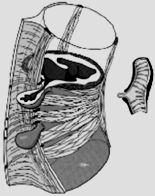

6.7.1 Diverticoli

del colon

La seguente radiografia a contrasto

mostra un esempio.